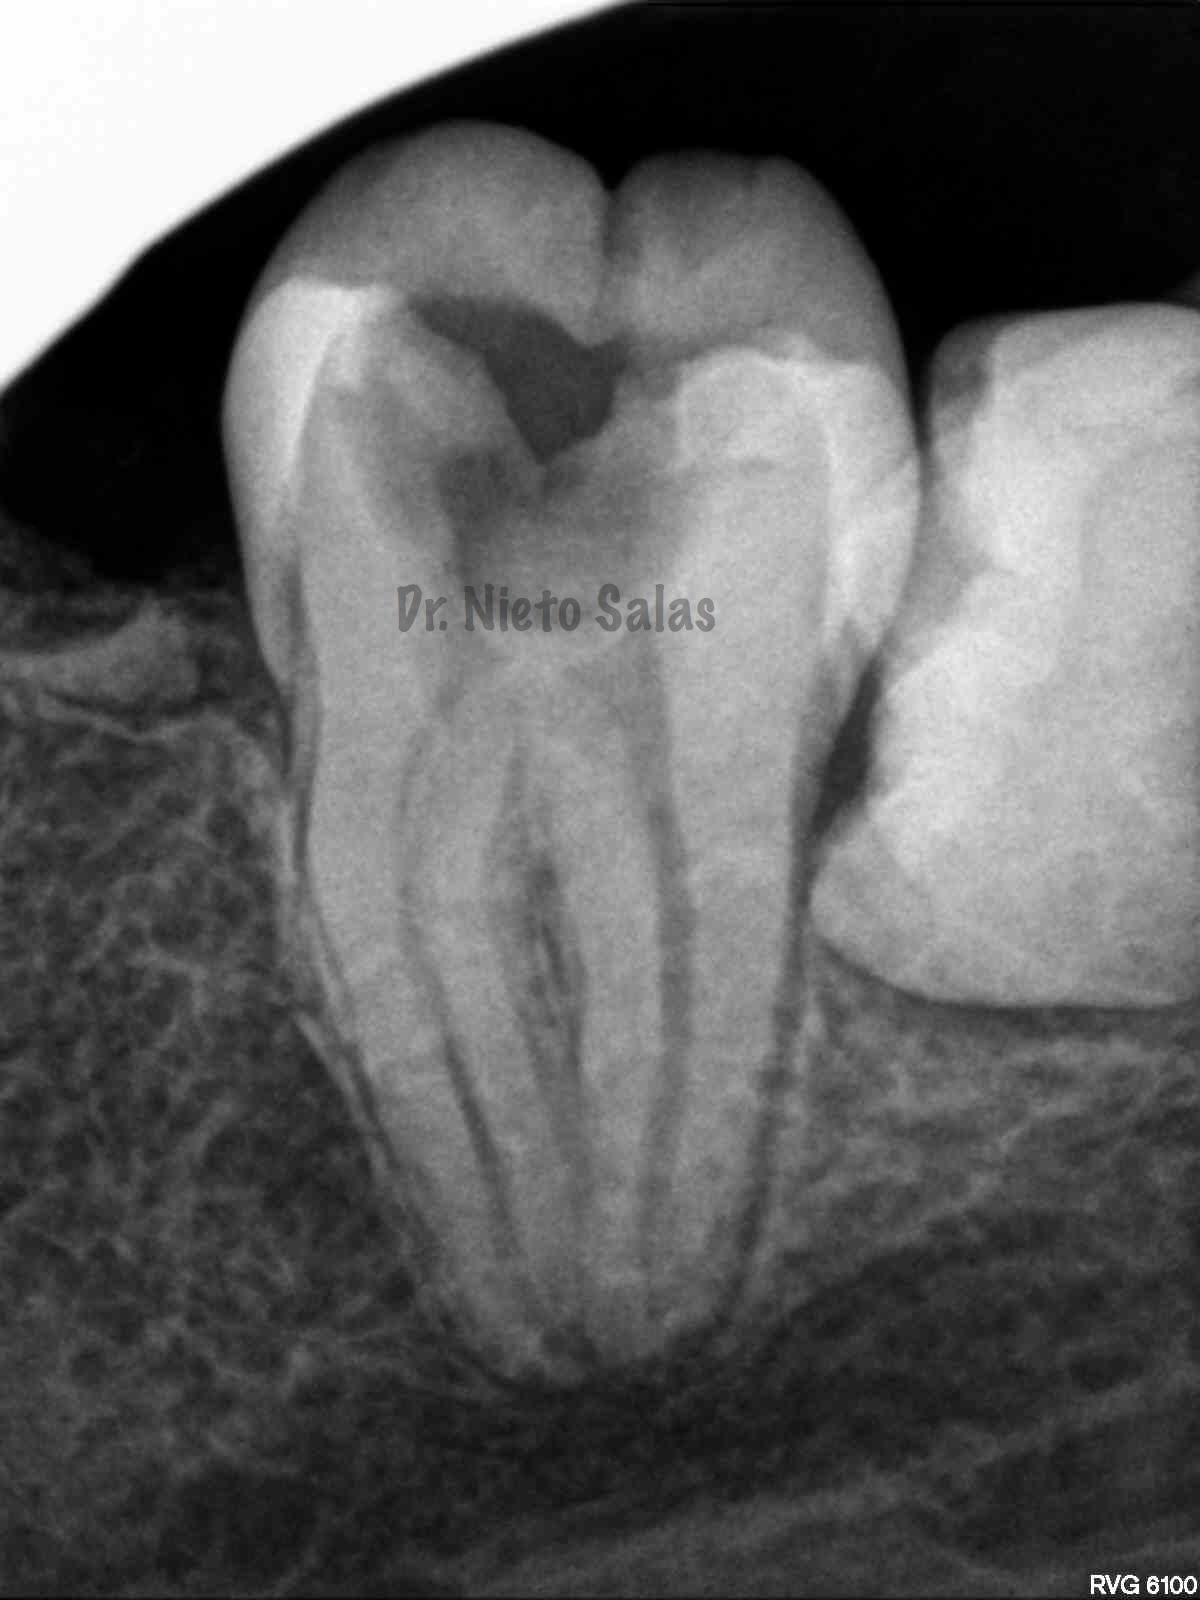

Así pues quedaría el sellado hermético y tridimensional:

La otra pieza, el 3.7, se instrumentó con sistema Protaper y obturación con Ola continua de Calor y un back-filling con la pistola Obtura II.

(buscamos siempre algún conducto lateral, para intentar asegurarnos de su limpieza)

Y una en las demás proyecciones MESIO Y DISTO: